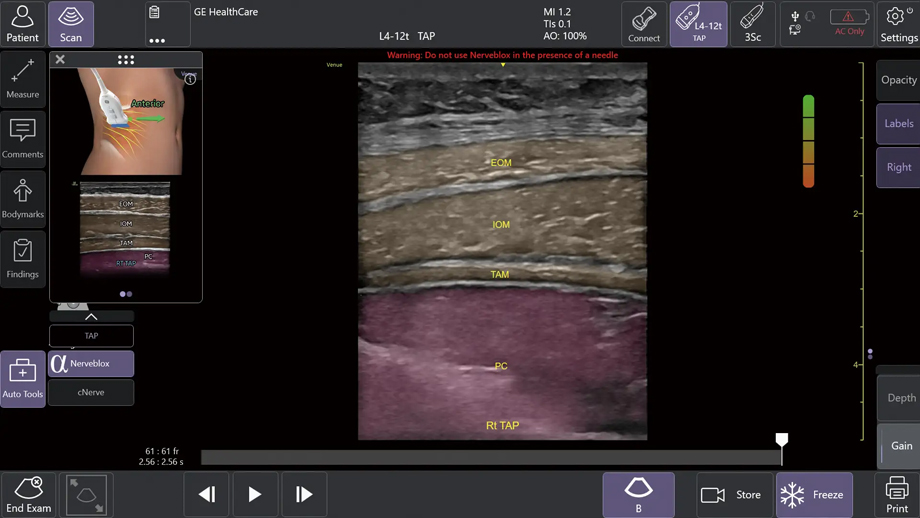

①AIツール Nerveblox(ナーブブロックス)で神経ブロック手技を効果的にサポート

AIを用いて開発されたNervebloxは、区域麻酔に用いられる標準的な12種類の神経ブロック部位に対して、神経および周囲組織(筋肉・血管・骨・筋膜など)をリアルタイムに認識し、ハイライト表示する機能である。

本機能は、画像クオリティを評価するQuality Meter、プローブの向きをガイドするOrientation表示、組織を色分けするカラーオーバーレイ、解剖構造名を示すアナトミカルラベル、理想的なプローブ位置を提示する模式図ガイド等を備え、走査者のエコー経験レベルに依存しない、より安定した神経描出をサポートする。

この機能により、麻酔科、救急科、集中治療科、整形外科など多くの診療科において、神経ブロック時の解剖学的構造の認識や視認性が高まることが期待され、よりスムーズな判断や手技をサポートする。

Nervebloxによる神経ブロックのサポート (中央)Anatomical Labeling: 画像上に解剖学的ラベルを略語形式で表示 (右上)Quality Meter:表示画像の品質をリアルタイムで評価して色分け表示